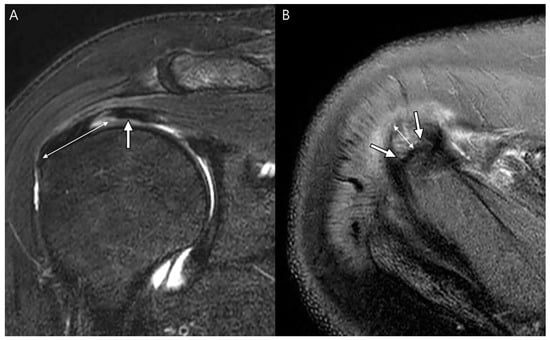

4. Radiologic Definition and Classification Using MRI

5. Radiologic Diagnosis of Delaminated Tears Using MRI